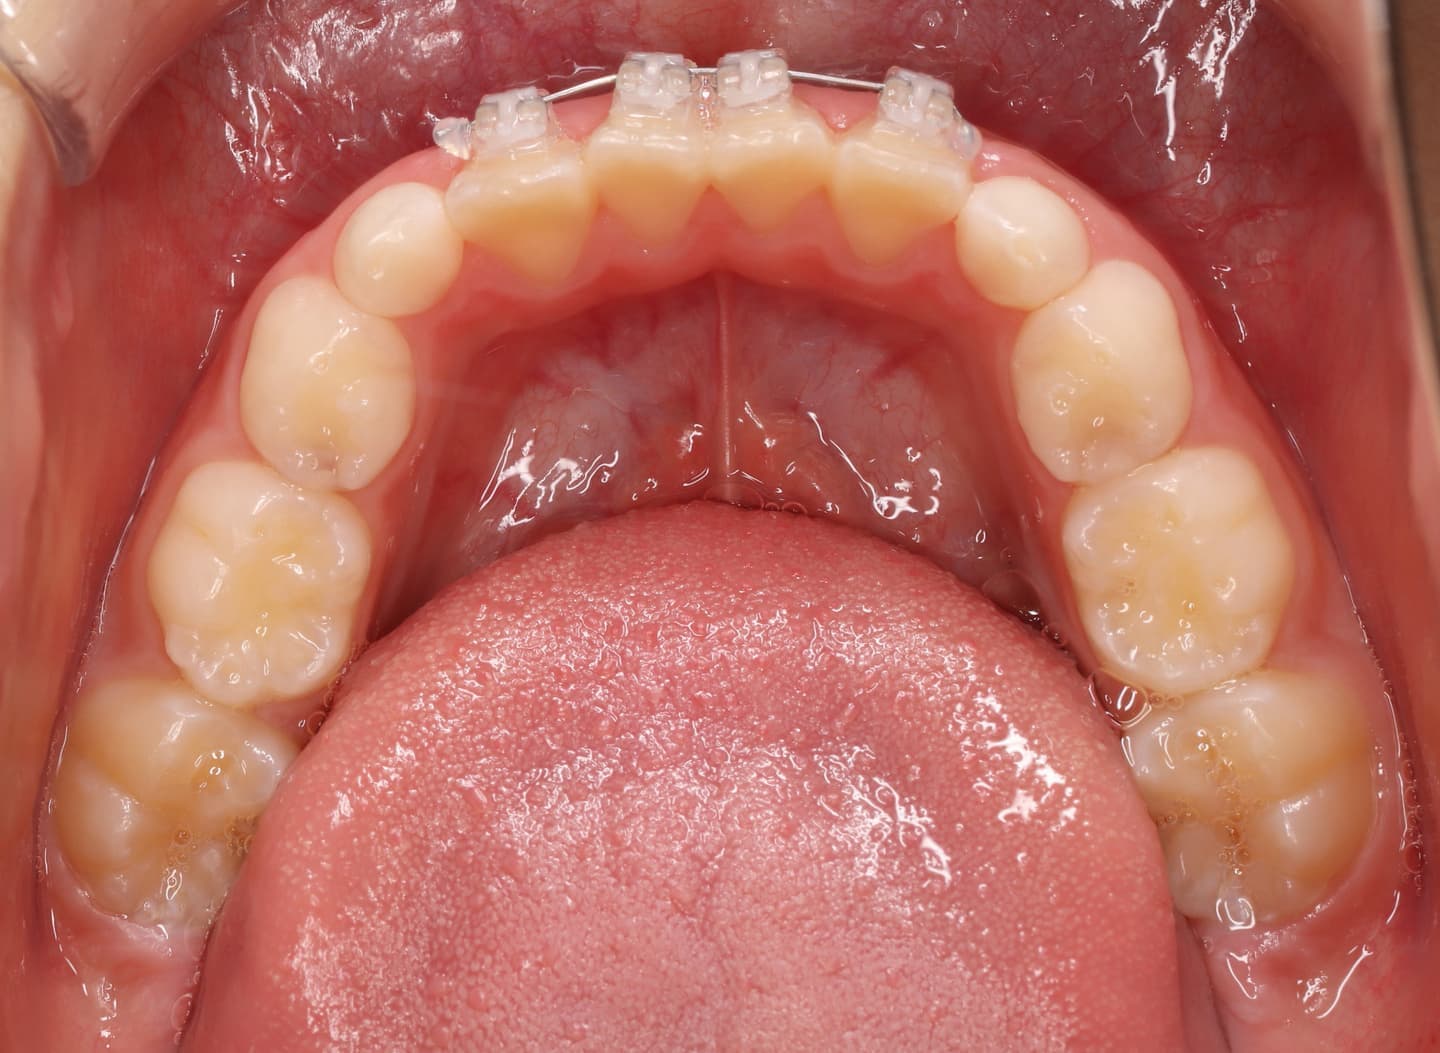

分析診断:FXフェイシャルアキシスが83度で、咬合力が極端に弱い顔面骨格ではありません。上下顎の骨格的バランスも平均値内には収まっています。Upper Molar PTV値から、上顎の奥行きが少ないとわかります。前歯の位置、E-lineと下唇の位置等から、歯が大きくて顎が小さいディスクレパンシーケースであると診断されます。

分析診断:左右の骨格的非対称が少し認められます。上顔面の幅径はさほど狭くなありませんが、下顎や下顔面の幅径は狭いと出ています。